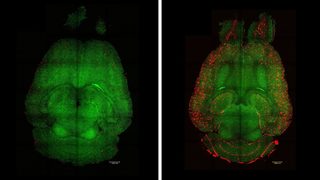

VIDEO Structuri necunoscute, descoperite în creier. Ar putea fi implicate în dezvoltarea bolii Alzheimer 6 oct 2025